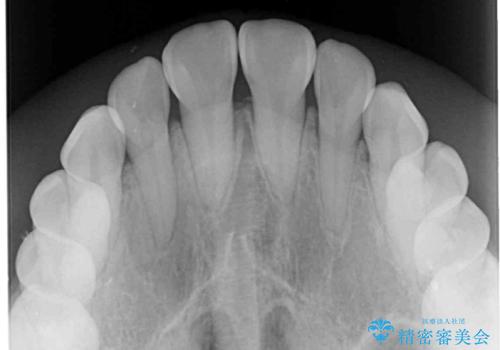

- 前歯の開咬と、受け口による咬み合わせの悪さを気にして来院された患者様です。

上顎歯列が狭窄していたため、急速拡大装置により上顎骨を側方に拡大し、その後ワイヤー装置にて矯正治療を行うこととしました。